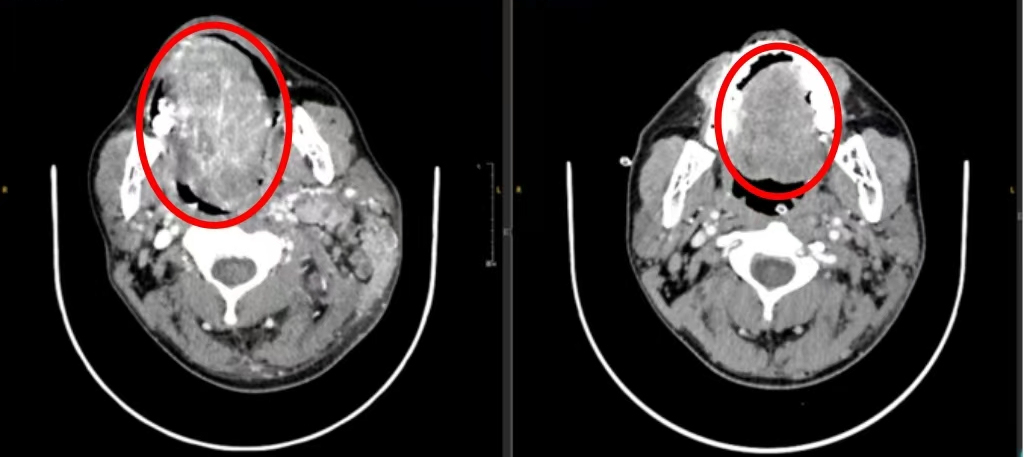

这名33岁患者的影像检查线上,肿瘤病灶从舌头转移到了颈部。